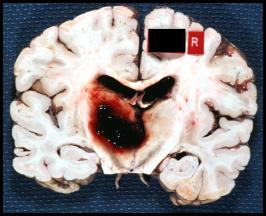

Hemorrhagic

Here are the corresponding coronal sections through the brain. Do these fit with your observations on the CT scans?